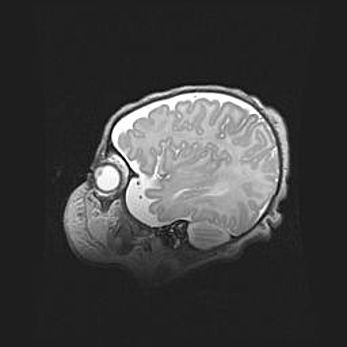

Подострая гематома правой гемисферы мозжечка.

Наружная гидроцефалия.

Возраст: 15 дней

Вес: 3100 г

Пол: женский

Окружность головы: 37 см

Срок гестации: 35-36 недель

При открытой наружной форме гидроцефалии у новорожденных расширяются и переполняются субарахноидные пространства.

Кровоизлияния в мозжечок имеют две клинико-анатомические формы: полушарные гематомы и кровоизлияния в червь.

К появлению этой патологии может привести: повреждения головного мозга, возникающие в результате асфиксии и гипоксии плода при беременности, или травмы во время родов. Редко гематома мозжечка может быть результатом первичной коагулопатии и сосудистой мальформации, диссеминированном внутрисосудистом свертывании, изоиммунной тромбоцитопении.